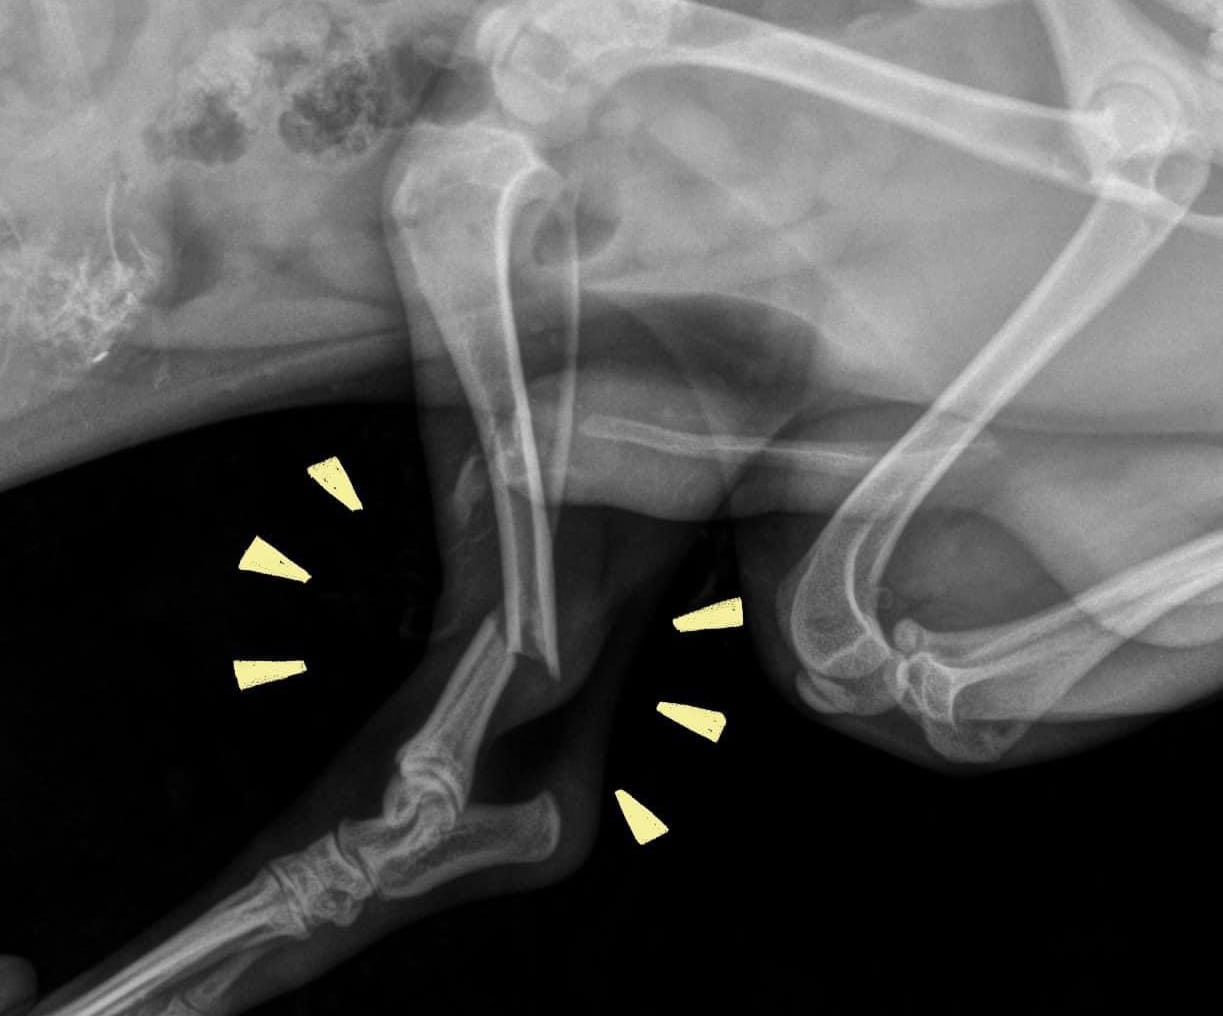

Falls from height (often called high-rise syndrome) can lead to severe injuries such as:

- Broken bones and fractures

- Internal bleeding

- Lung trauma or breathing difficulty

- Head and spinal injuries